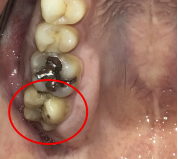

右下のブリッジがゆらゆら動く。

治療内容

ブリッジの支台になっている奥の歯が、被せ物の中で虫歯になり、支台の役割を果たさず、前方の歯のみで支えられていました。前方の歯をそのままにして、後方の部分を切り離すと、そのまま取れてきました。中は、虫歯で歯根しか残っていない状況でした。この歯は、根管治療後、単独でオールセラミック冠を被せ、歯のないところにインプラントを埋入しました。

Before

冠の中で大きな虫歯になり支台の役割を果たしていませんでした。

【インプラント埋入前】

冠はブリッジを切断しただけで取れてきました。軟化象牙質を取り除いたところ、歯根しか残っていない状況で保存できるかどうかのぎりぎりのところでした。

After